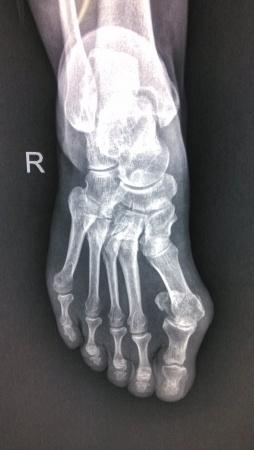

患者女性47岁,近期没有任何足外伤史(反复询问),于2个月前无诱因出现又足背部疼痛,走路时间长疼痛加重。请帮忙看下这个X光片有什么问题。 侧位看的不清楚

正位掌骨。

我和大家考虑一样,拇外翻肯定是有的。

拇趾外翻,足舟骨那个裂隙不是问题经常见,应该是投照较多问题,可以透视下变换**观察下

第一跖趾关节滑膜炎,第一跖骨头可见圆形低密度改变,不排除通风骨质改变。